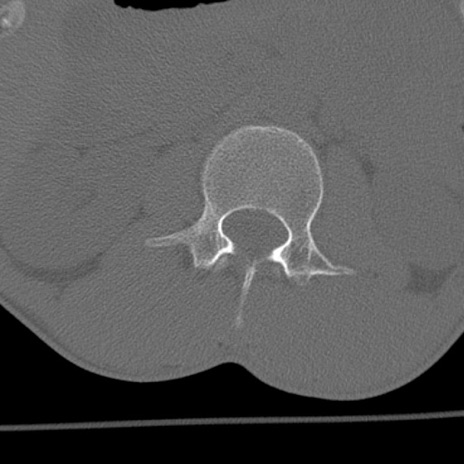

症例3 腰椎CT(横断像)

腰椎CT